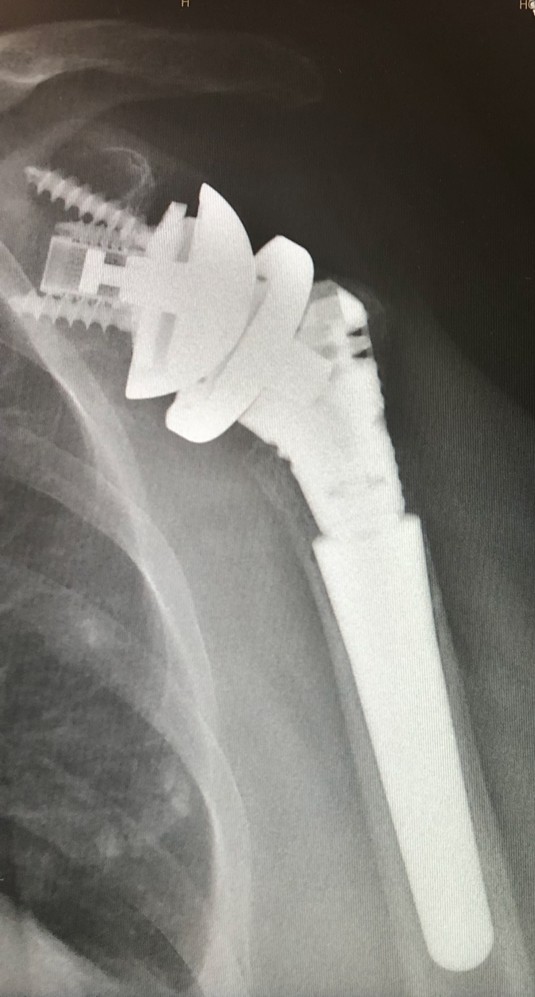

Post-op

Implantation of the Link Embrace

- RSA

- Modular Revision Stem, 75 mm, cementless

- Proximal Body height 45 mm

- Humeral Reverse Tray, neutral

- Eccentric Glenosphere ø 36 mm with PE-Insert height 0

- Reverse Glenoid Baseplate with 2 compression screws and 1 locking screw